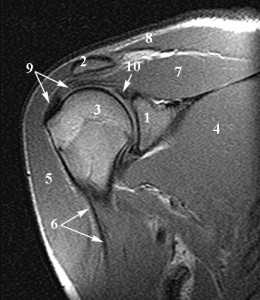

Анатомия плечевого сустава. Т1-зависимая МРТ в корональной плоскости. Обозначения: 1 -суставная (гленоидная) впадина, 2 - ключица, 3 -головка плечевой кости, 4 - подлопаточная мышца, 5 - дельтовидная мышца, 6 - длинная головка сухожилия двуглавой мышцы плеча, 7 - надостная мышца, 8 - трапецевидная мышца, 9 - сухожилие надостной мышцы, 10 - верхняя губа.